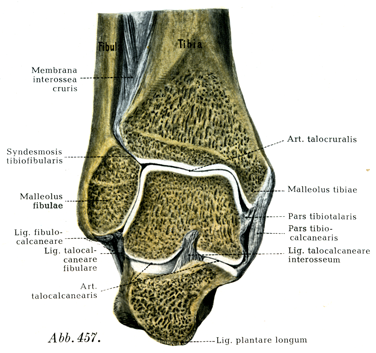

[図457] 右の下腿骨と足骨の前額断 断面を前方からみる.

特別の装置として6つの側副靱帯があへそのうち3つが脛骨踝から,他の3つが腓骨踝から起る.脛骨からの3つの靱帯は密に相接して三角靱帯Lig. deltoidesとよばれる三角板を形成する.

三角靱帯の脛舟部Pars tibionavicularisは幅およそ5mmで,脛骨踝の前縁と先端から起って,舟状骨の上面と内側面につく(図459, 463)

三角靱帯の脛踵部Pars tibiocalcanearisは幅およそ1cmで,はなはだ丈夫である.脛骨踝の外面から起って踵骨の載距突起につく.その最前部の線維束は踵舟靱帯に移行している(図457, 459)

三角靱帯の脛距部Pars tibiotalarisはFickによれば幅およそ15mm,厚さ約5mmである.後脛骨筋の腱鞘によって被われ,脛骨踝の下縁から起って斜め下方に走り,距骨滑車の脛側踝面の縁につく(図458, 459)

前距腓靱帯Lig. fibulotalare anteriusは腓骨踝の前縁から起り,距骨滑車の腓側踝面の前縁につく.幅は約1cmで,あまり丈夫なものではない(図460, 463).

踵腓靱帯Lig. fibulocalcaneareは腓骨踝の前縁の下部から起り(先端からは起らない),斜め後下方に走って踵骨の外側面につく.幅8mm,厚さ5mm,長さ2cmほどである(Fick).この靱帯の外側を長・短腓骨筋の腱が走っている(図457, 458, 460, 463)

後距腓靱帯Lig. fibulotalare posteriusはほぼ水平に走る.腓骨踝窩から起り,距骨の近位突起につく.この靱帯は3つの外側の靱帯のうちで最もつよい(図458).